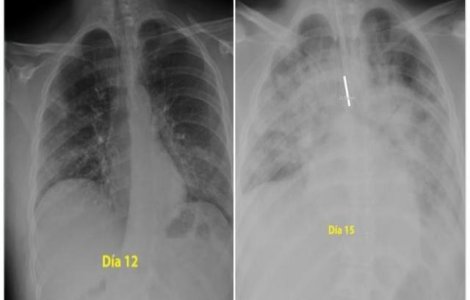

Radiografia unei persoane infectate cu Covid-19 arată efectul dramatic pe care îl are virusul asupra plămânilor pacienților.